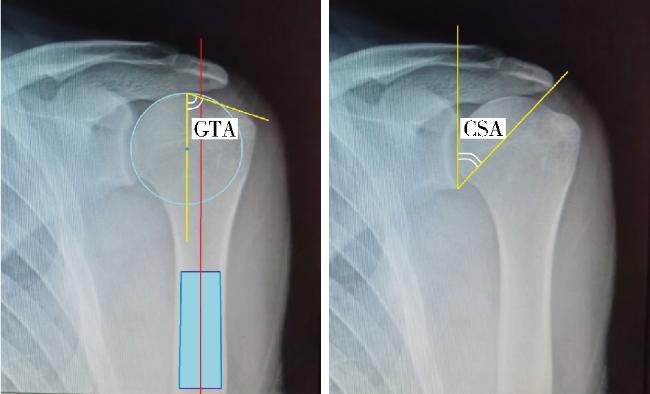

图2 GTA和CSA在肩胛骨正位X线片上的测量方法Figure 2 Measurement methods of GTA and CSA on apraxis of scapula Greater tuberosity angle (GTA) is made by two crossing lines. The first line passes through the center of humeral head and parallels to the humerus diaphysis, and the second one connects the upper border of the humeral head to the most superolateral edge of the greater tuberosity. Critical shoulder angle (CSA) consists of the angle with two crossing lines. One of which was drawn from the glenoid superior to inferior border, the other was drawn from the glenoid inferior border to lateral aspect of the acromion. |